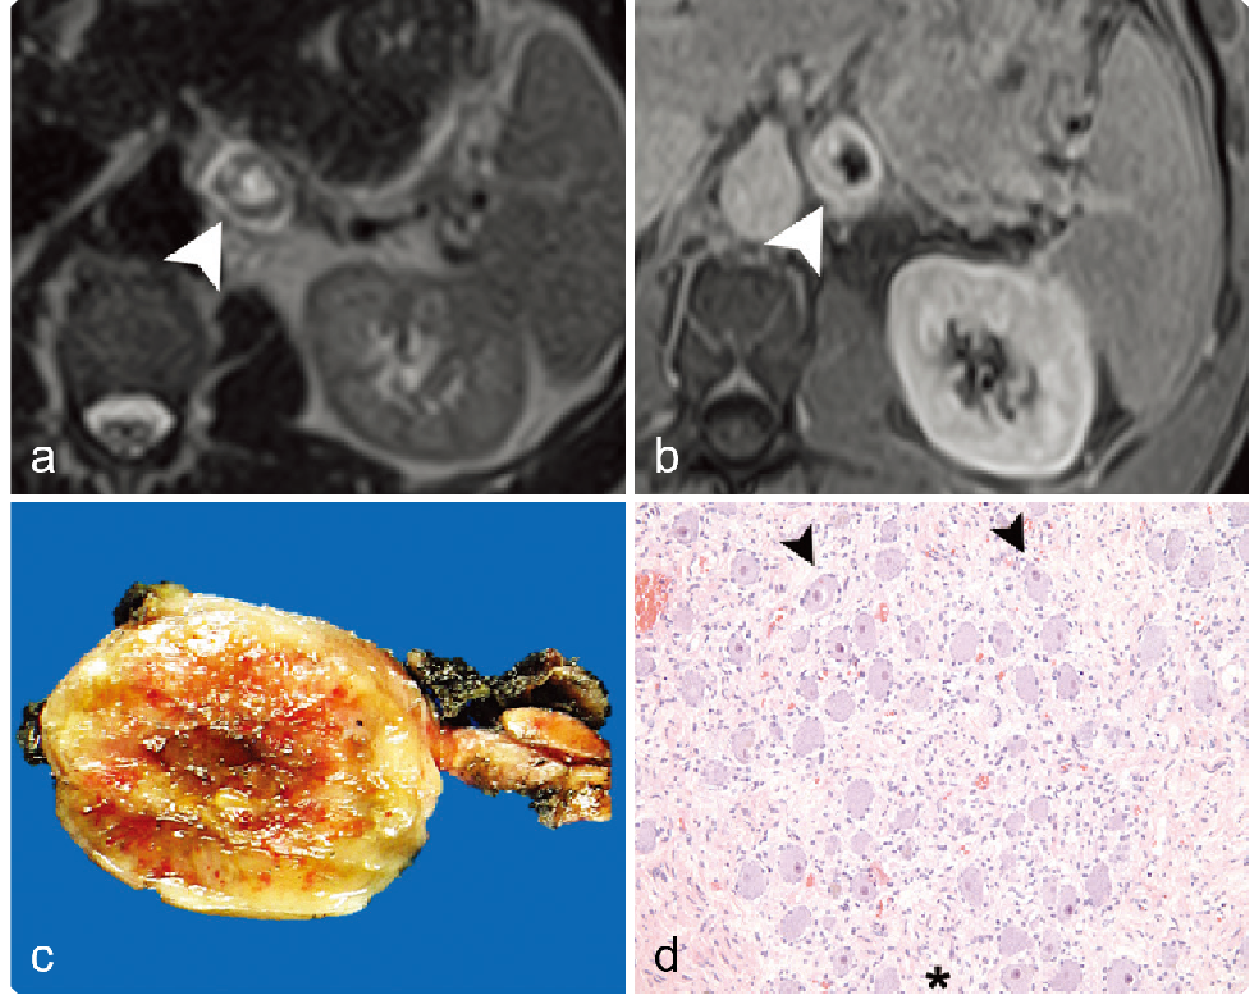

0a5fb18a3933294f8c258284440d05bf.png 病例 8:腹膜后(血管外)平滑肌肉瘤  46岁女性 腹膜后肿物不均质强化,病灶与前方下腔静脉、上方肾上腺及下方肾脏分界清晰,病灶侵犯右侧腰大肌。瘤内少量出血,不均质强化,弥散受限。大体病理显示瘤内出血、坏死;镜下:具有有丝分裂和核异型的梭形细胞。